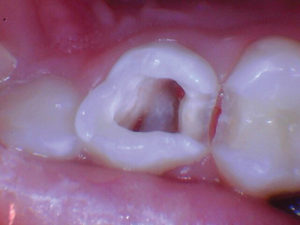

Caso 5

Una adolescente de 13 años presentada para un nuevo examen de paciente. Se observó una gran lesión cariosa en el primer molar permanente superior izquierdo, que presentaba síntomas de pulpitis reversible. Las opciones de tratamiento se discutieron con la paciente y su madre. Mis objetivos personales para este caso eran evitar la exposición de la pulpa y restaurar la forma y la función.

Figura 1. Presentación

clínica inicial del primer molar permanente superior izquierdo con caries

oclusal. |

Figura 2. Cuando la lesión

estaba sin techar, era evidente que había una lesión amplia y profunda. |